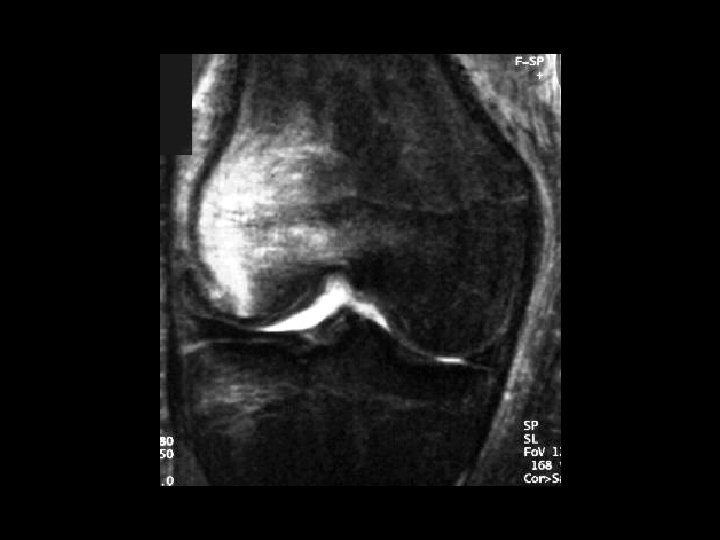

Bucket-Handle Tear • Findings: – “double PCL sign” - torn meniscus BELOW normal PCL on sag view – Above ACL on cor view – Truncation of medial meniscus – Joint effusion • Medial = 3 x lateral • Locked knee • ddx: – torn ACL, PCL – torn meniscus